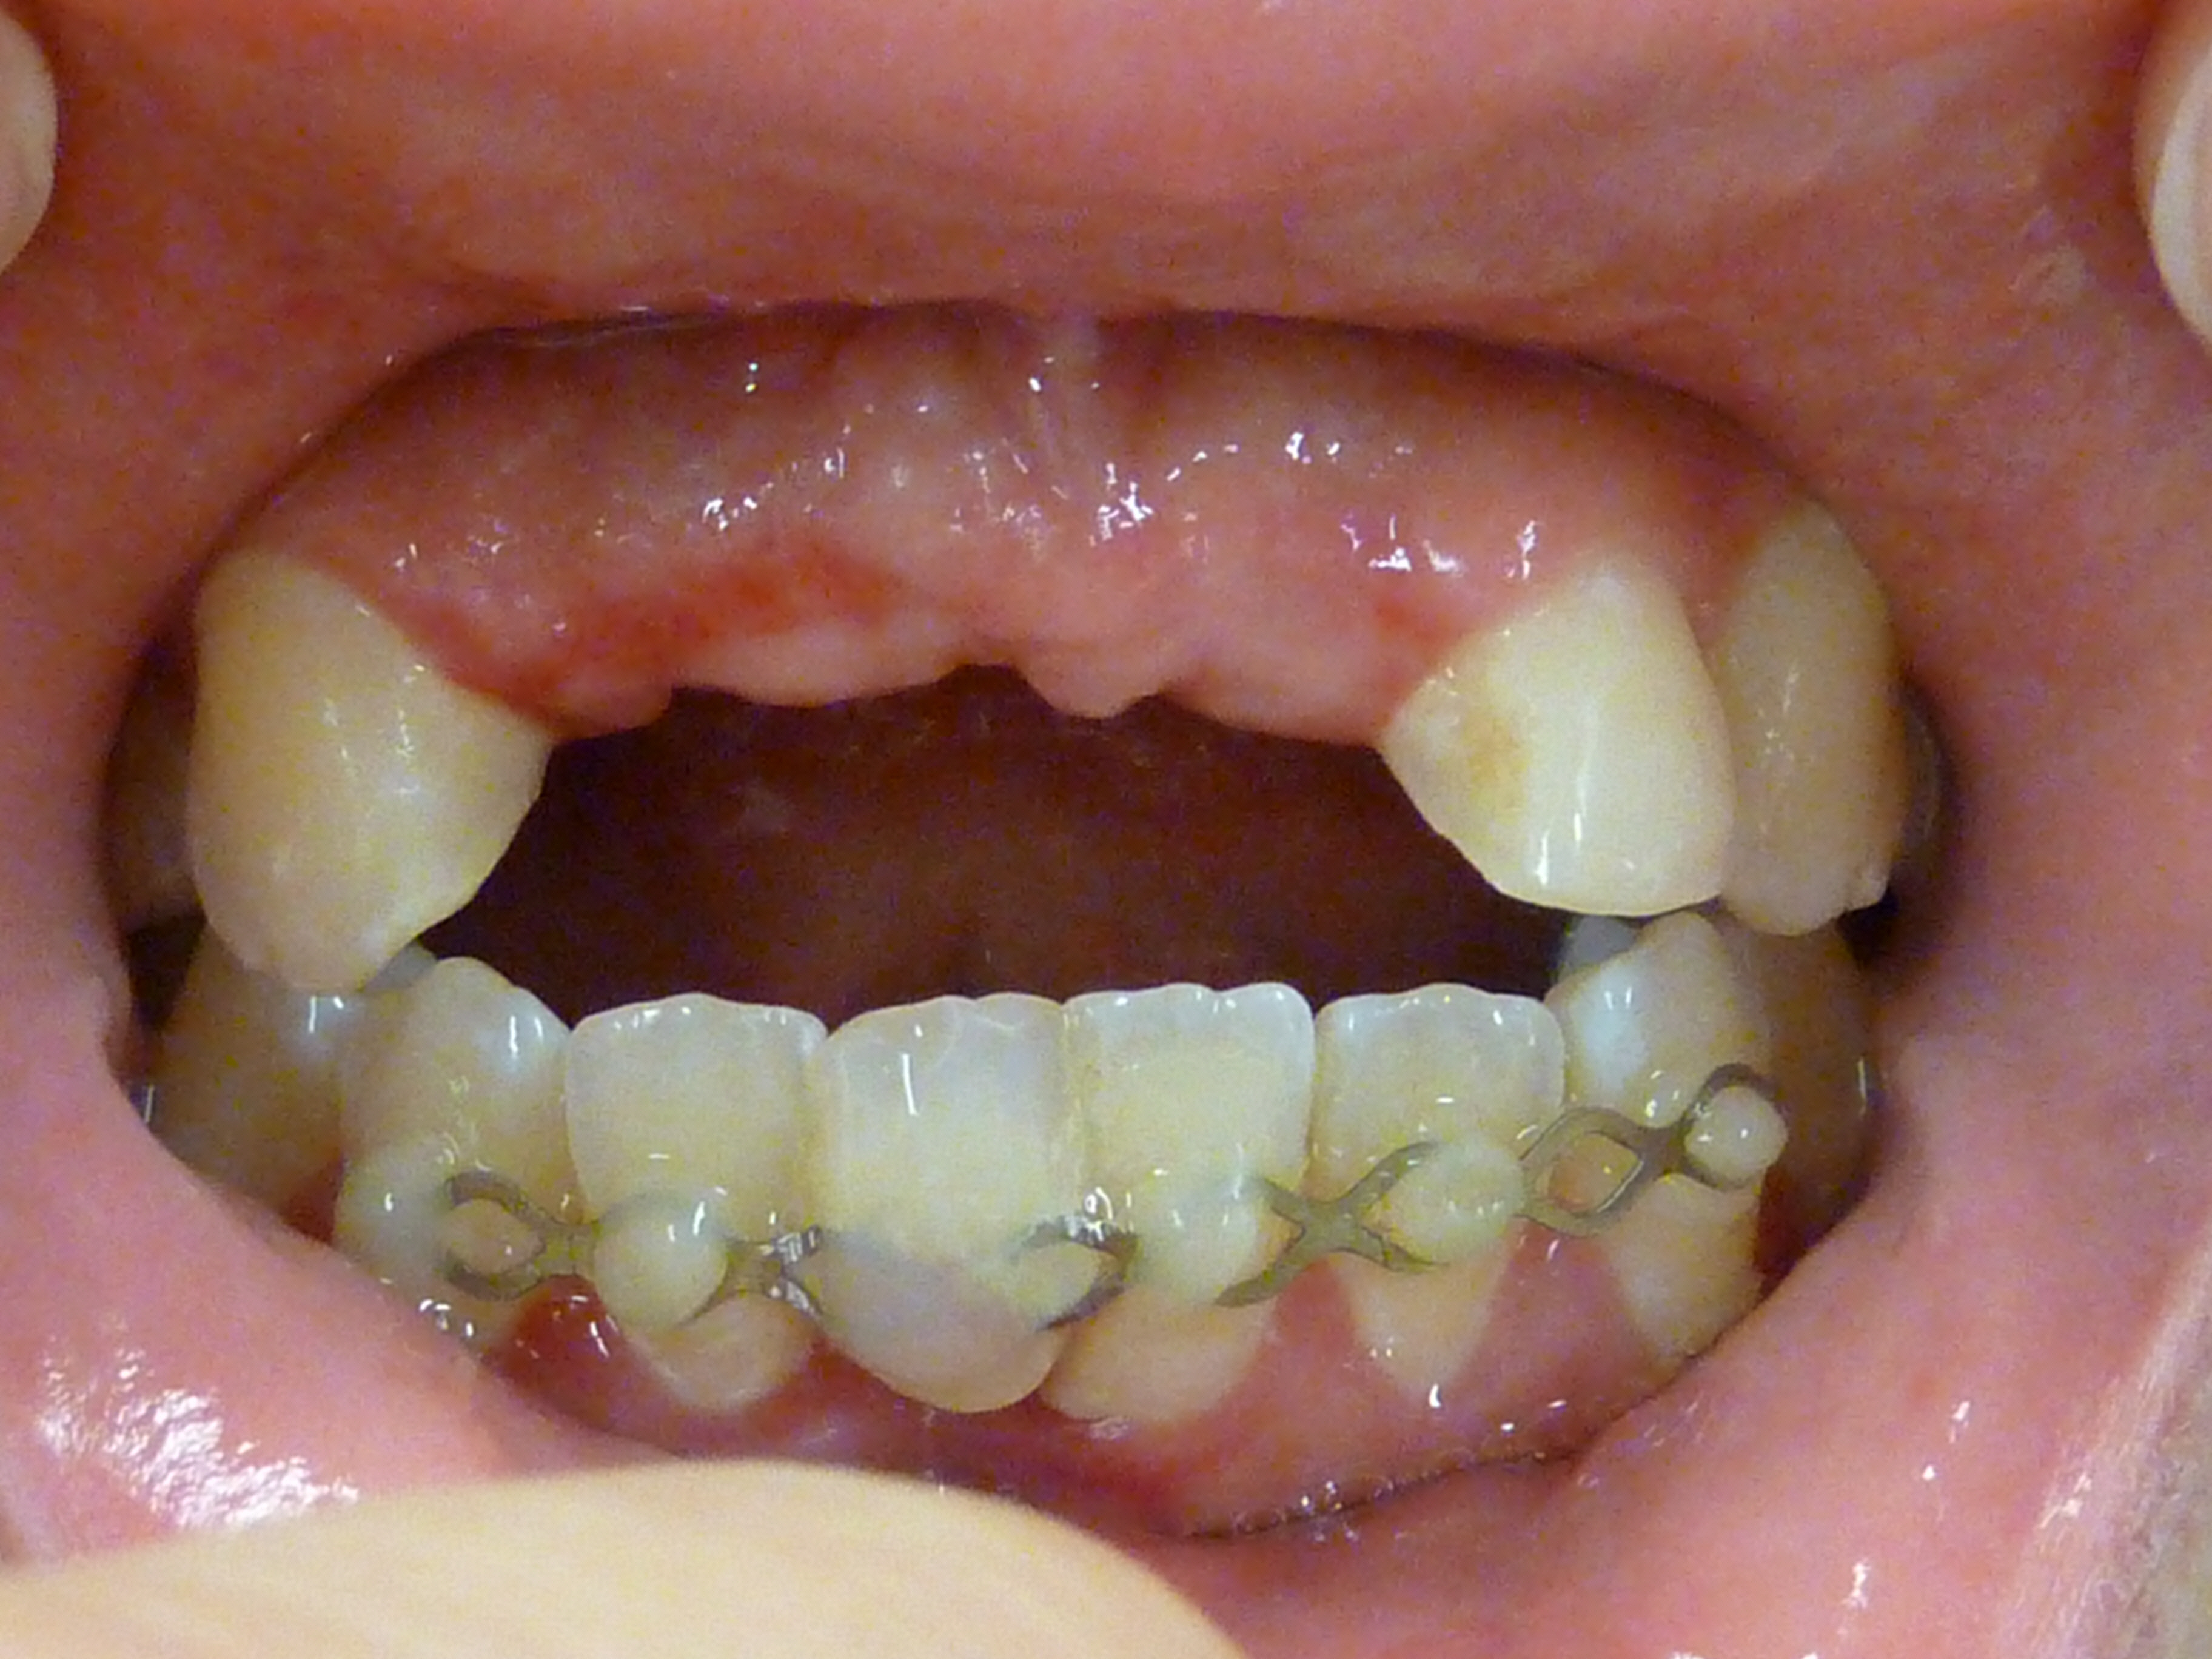

Diastèmes disgracieux et absence des incisives latérales

Après traitement orthodontique, implant Straumann, couronne et facettes Edelweiss